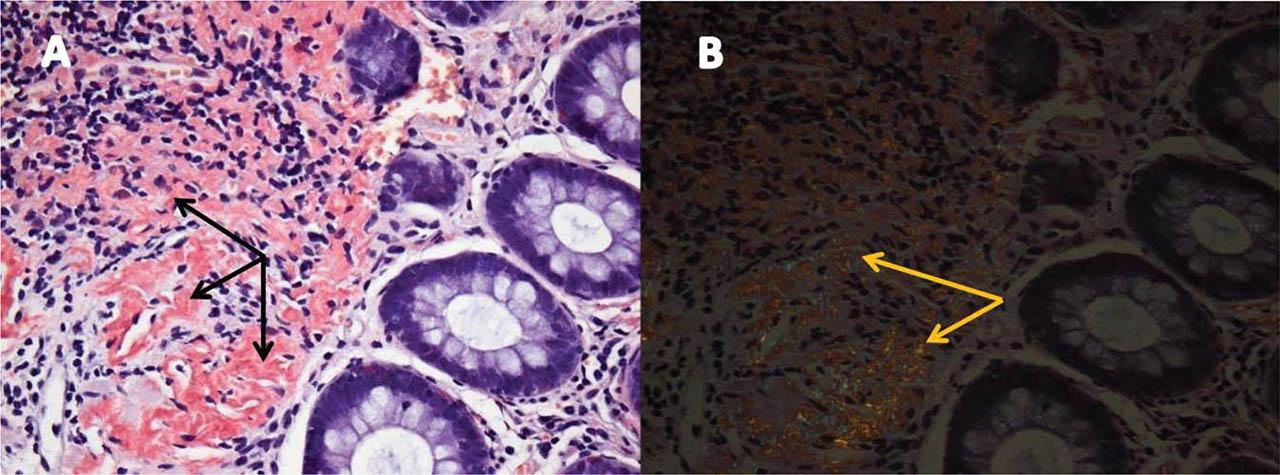

Figure 7

Rectal pad biopsy images showing A. homogenous extracellular fibrils positive for Congo red staining localized in the vascular walls (black arrows); B. These fibrils are positive for green birefringence, specific for amyloid deposits (yellow arrows).